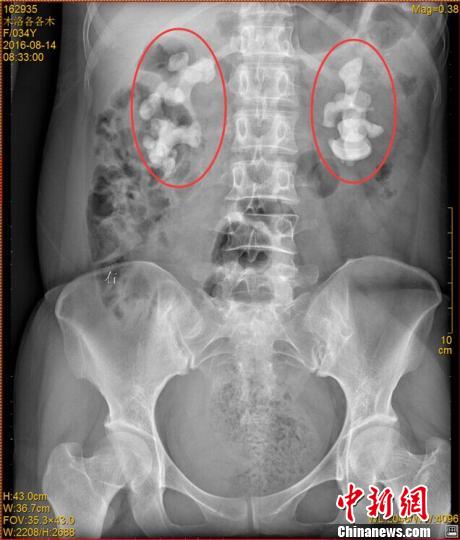

各各木術(shù)前影像圖片,紅圈內(nèi)為巨大腎結(jié)石!$娦馈z

中新網(wǎng)成都11月7日電 (王鵬)記者7日從四川省結(jié)石病醫(yī)院獲悉,該醫(yī)院近日收治了一名罕見(jiàn)腎結(jié)石病人。來(lái)自四川涼山的34歲女子各各木,雙腎長(zhǎng)出10厘米巨型結(jié)石,腎內(nèi)空間幾乎全被結(jié)石填滿。

“臨床上,雙腎長(zhǎng)巨大結(jié)石的患者一般都是中老年男性,女性較為少見(jiàn),年輕女性更加罕見(jiàn)!彼拇ㄊ〗Y(jié)石病醫(yī)院常立高醫(yī)生詳細(xì)檢查后發(fā)現(xiàn),該女子雙腎內(nèi)空間幾乎被結(jié)石全部填滿。他詢問(wèn)患者后判斷,該罕見(jiàn)病例的出現(xiàn)與女子常年喝生水有直接關(guān)系。